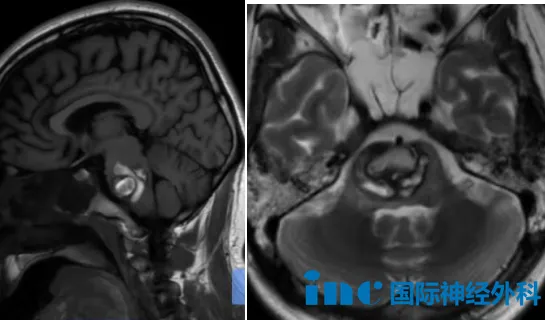

患者4:何女士(53岁)

五十三岁的何女士同样被脑干海绵状血管瘤所困。然而在咨询巴教授后不久,病情猝然加重——肿瘤在短时间内增大并再次出血,症状从最初的轻微麻木、头晕,迅速进展为四肢无力、言语不清。巴教授在术前谈话时说:"还好这一次终于可以手术了。"此刻的她,面对曾经被称为"生命禁区"的病变,反而出奇平静,满心期待着即将到来的手术。